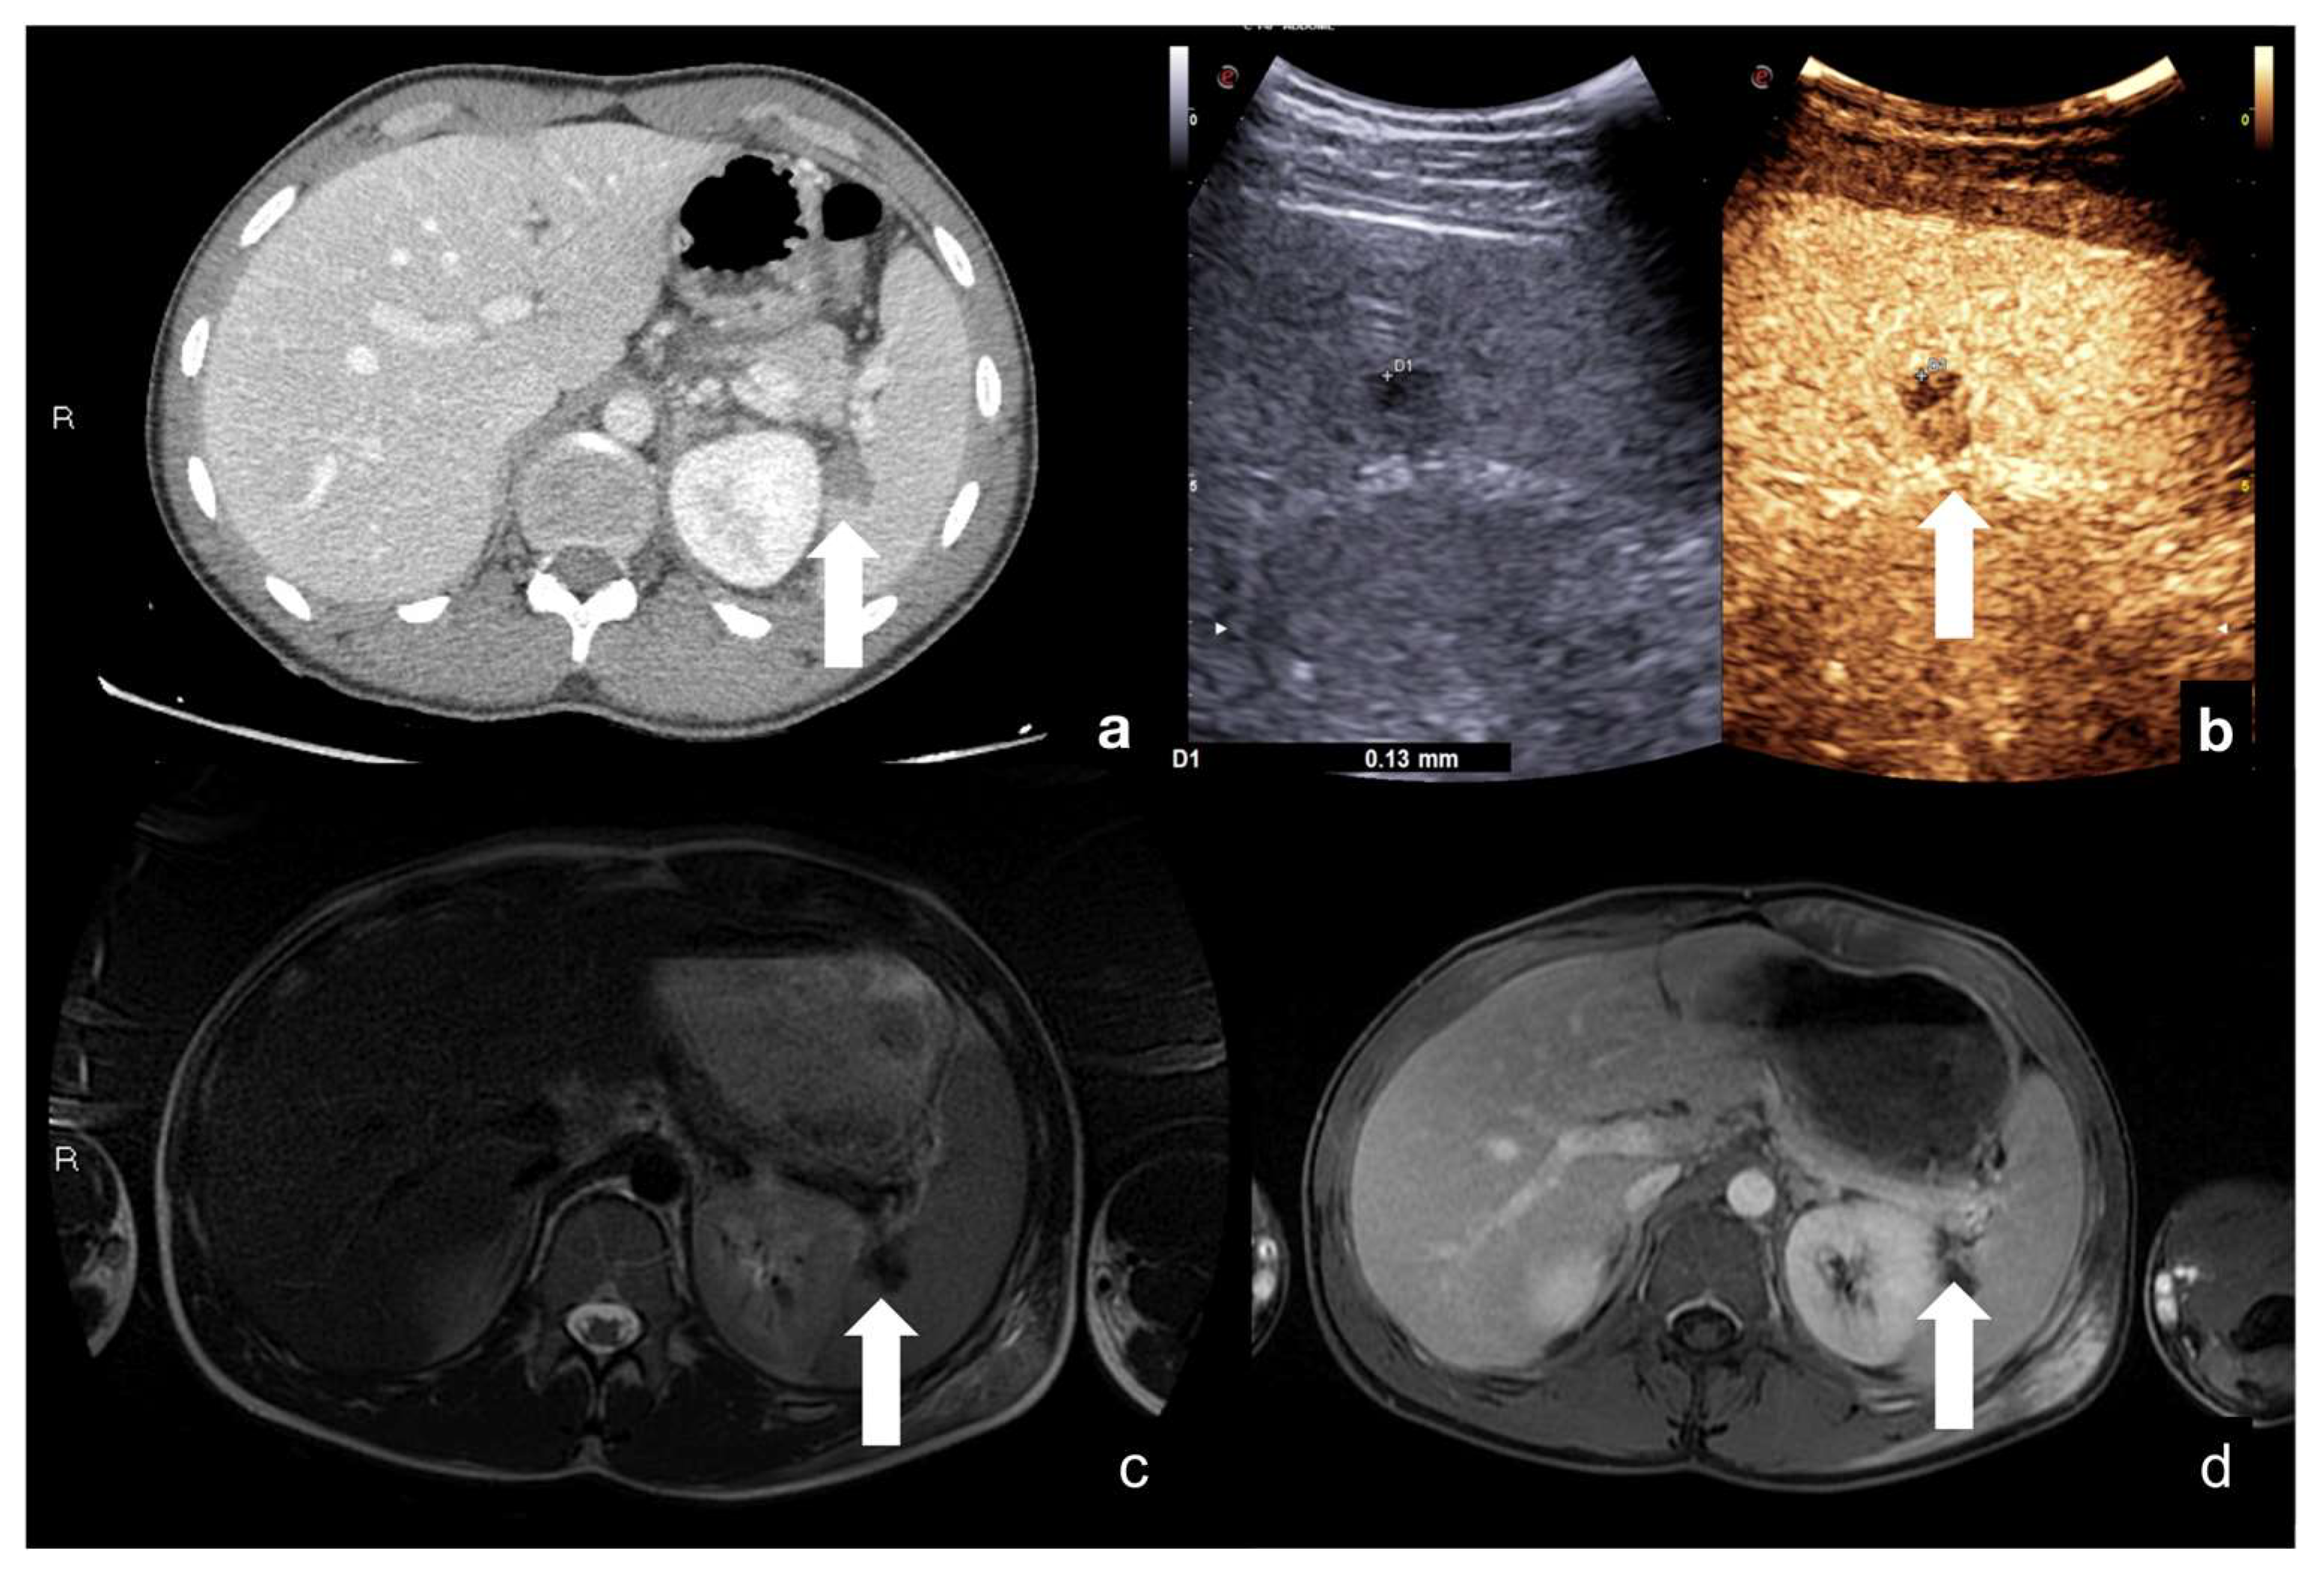

2.3.1. Solid Organ Injuries May Involve the Parenchyma and the Vessel

- Parenchymal injuries:

4. Case Series: Step-by-Step Practical Applications, Tips and Tricks during CEUS Follow-Up of Conservatively Managed Abdominal Trauma

4.1. Step 1

4.2. Step 2

4.3. Step 3

4.4. Step 4

4.5. Step 5